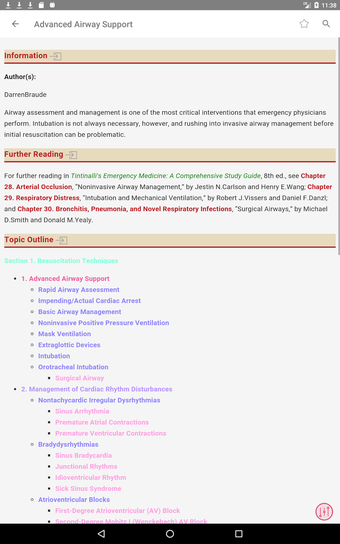

最初に知っておくべきことは、ティンティナリの緊急医療マニュアルが緊急医療の最も重要なトピックについてすべてを提供する包括的なガイドであることです。これは、医師、看護師、および救急医療技師にとって理想的なアプリです。

この無料アプリには、日常の実践に役立つ多くの情報が含まれています。このアプリでカバーされるトピックは、疾患から薬剤、さまざまなタイプの傷害まで幅広く、患者ケアを担当する人々にとって素晴らしいリソースです。